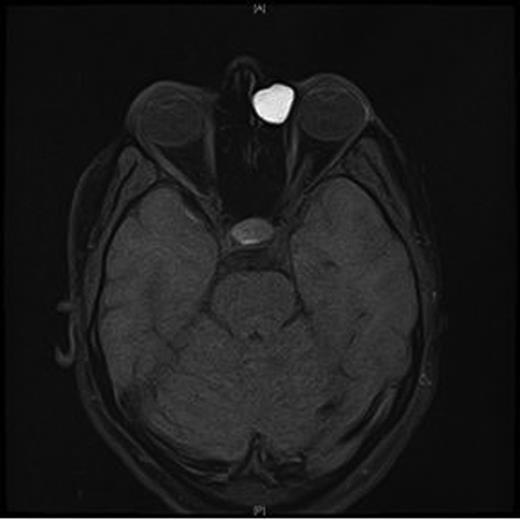

An MRI scan of the orbits showed a well-defined, thin-walled 22 × 16 mm cyst medial to the left orbit containing fatty/proteinaceous material, which was lying within and mildly expanding the left ethmoid air cells (Figs 1–3).